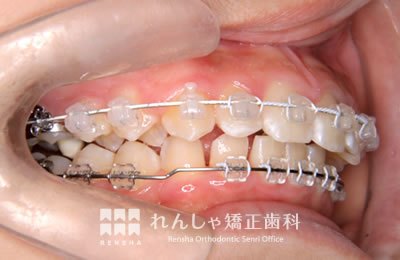

中高生

永久歯列はほぼ完成してしますが、歯列を側方だけでなく後方へも拡大し、埋まっていた右上奥歯を引っ張り出しています。

治療中

→

治療後

| 主訴 | 埋まったままでてこない歯がある |

|---|---|

| 診断名 | Angle Class II 小臼歯の埋伏と叢生を伴う上顎前突 |

| 初診時年齢 | 13歳5か月 |

| 装置名 | マルチブラケット装置 |

| 抜歯非抜歯 | 非抜歯 |

| 治療期間 | 2年3か月 |

| 費用の目安 | 約82万円+消費税(検査料金、都度の処置費用等も合わせた総額) |

| リスク副作用 | 歯の移動に伴う軽微な歯根吸収、歯槽骨吸収、歯肉退縮(本症例では軽度の歯根吸収を認めた)、矯正器具装着中のカリエスリスク増大(本症例ではカリエス発生無し) |